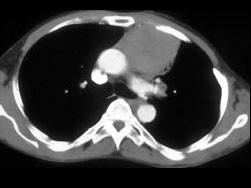

男,57岁,胸部隐痛2月余,请结合影像学检查,选出最可能的诊断 ( )A、胸内甲状腺肿B、胸腺瘤C、淋巴瘤D、支气管囊肿E、纵隔畸胎瘤

问题 男,57岁,胸部隐痛2月余,请结合影像学检查,选出最可能的诊断 ( )

选项 A、胸内甲状腺肿 B、胸腺瘤 C、淋巴瘤 D、支气管囊肿 E、纵隔畸胎瘤

答案 B